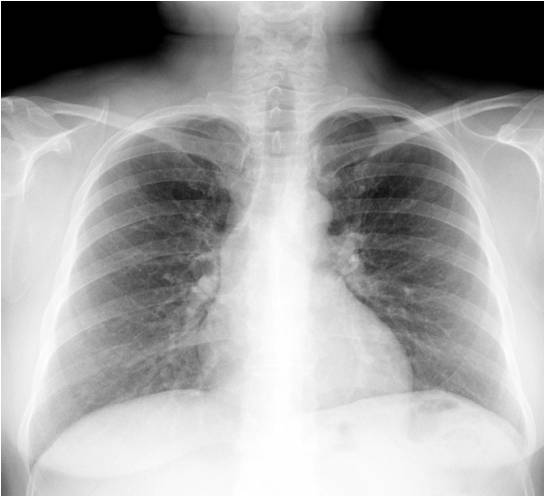

Не совсем, Игорь Иванович, сравни пожалуйста зоны надплечий с обеих сторон-вывод сам на язык напросится...

Видать лимфоузлы. Молочная???

В "десятку", Анатолий Владимирович - пакет увеличеных надключичных л\узлов справа, именно с жалобами на наличие припухлости там и обратилась больная к хирургу, итог - рак молочной железы....увы....жаль, что у нас нет маммографа и маммограммы практически никогда не попадают...

Я еще присматривался к высокому левому куполу - не рак желудка ли с мета Вирхова, но он вроде слева должен быть.